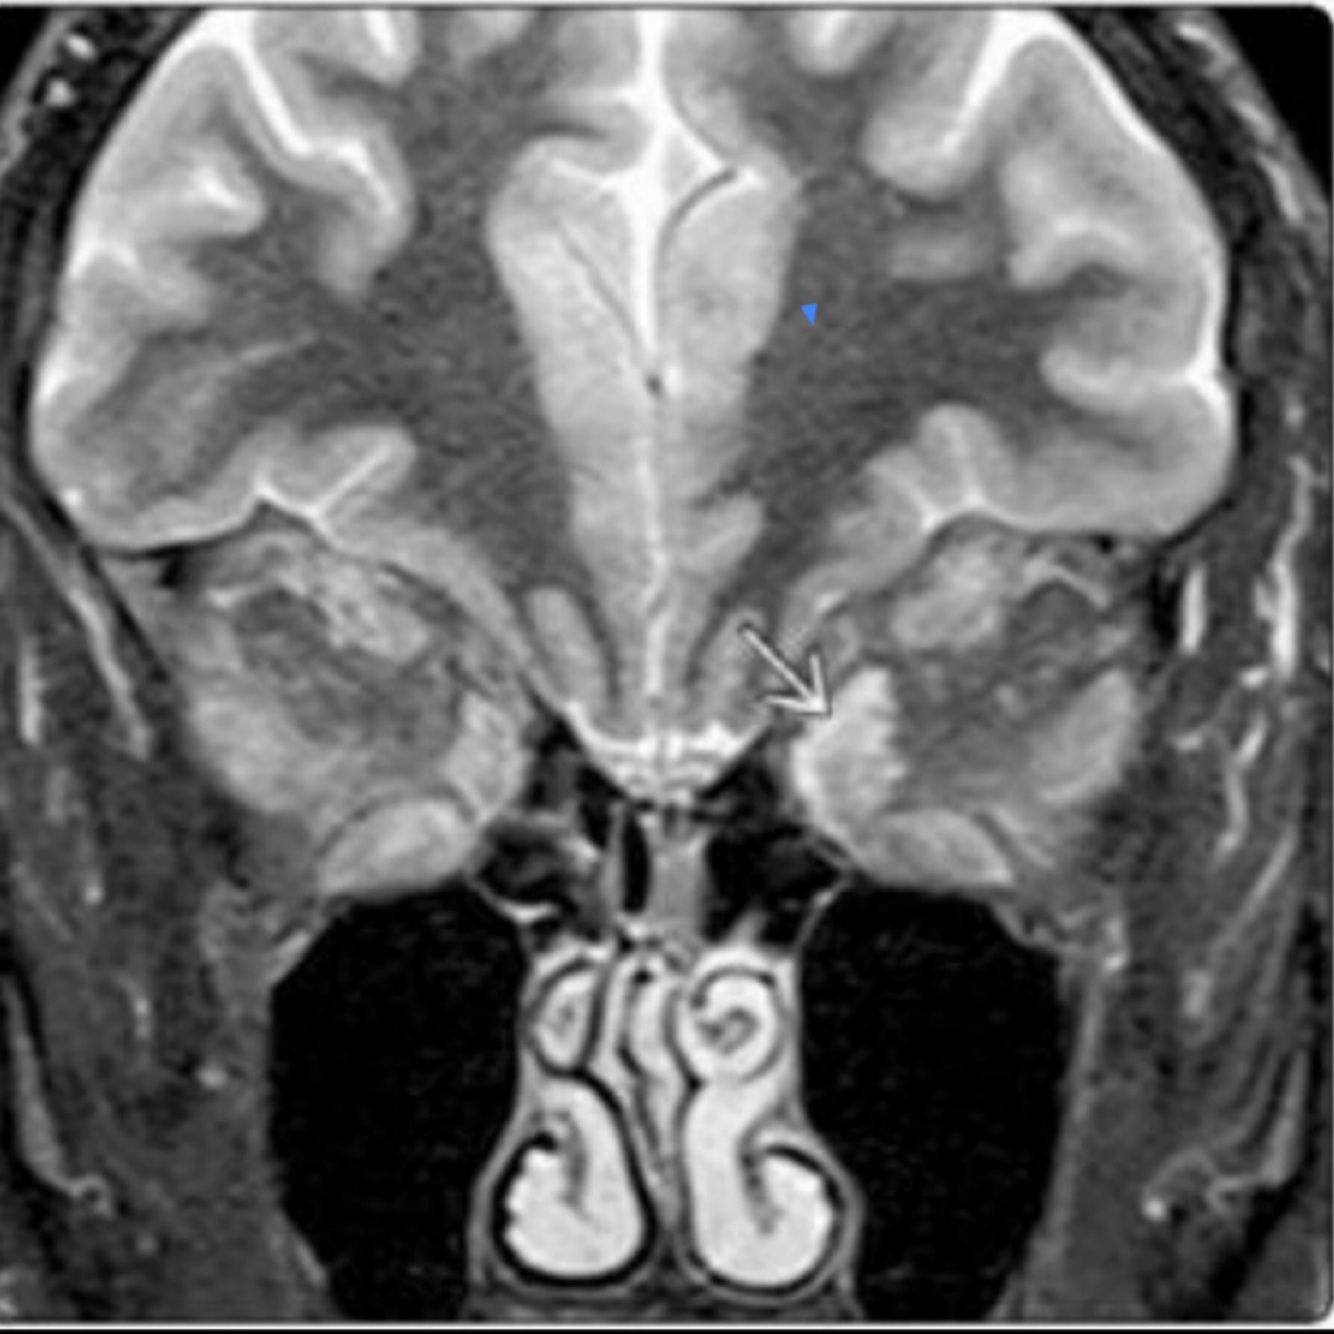

Resonancia Magnética relevancia:

A

• Tratamiento

• Compromiso de N. óptico

Mejor estudio

T1

Orbitopatía tiroidea

Hallazgos en T2:

Fases

• Aguda: aumenta señal en músculos

• Crónica: baja densidad

Diámetro disminuido en N. óptico